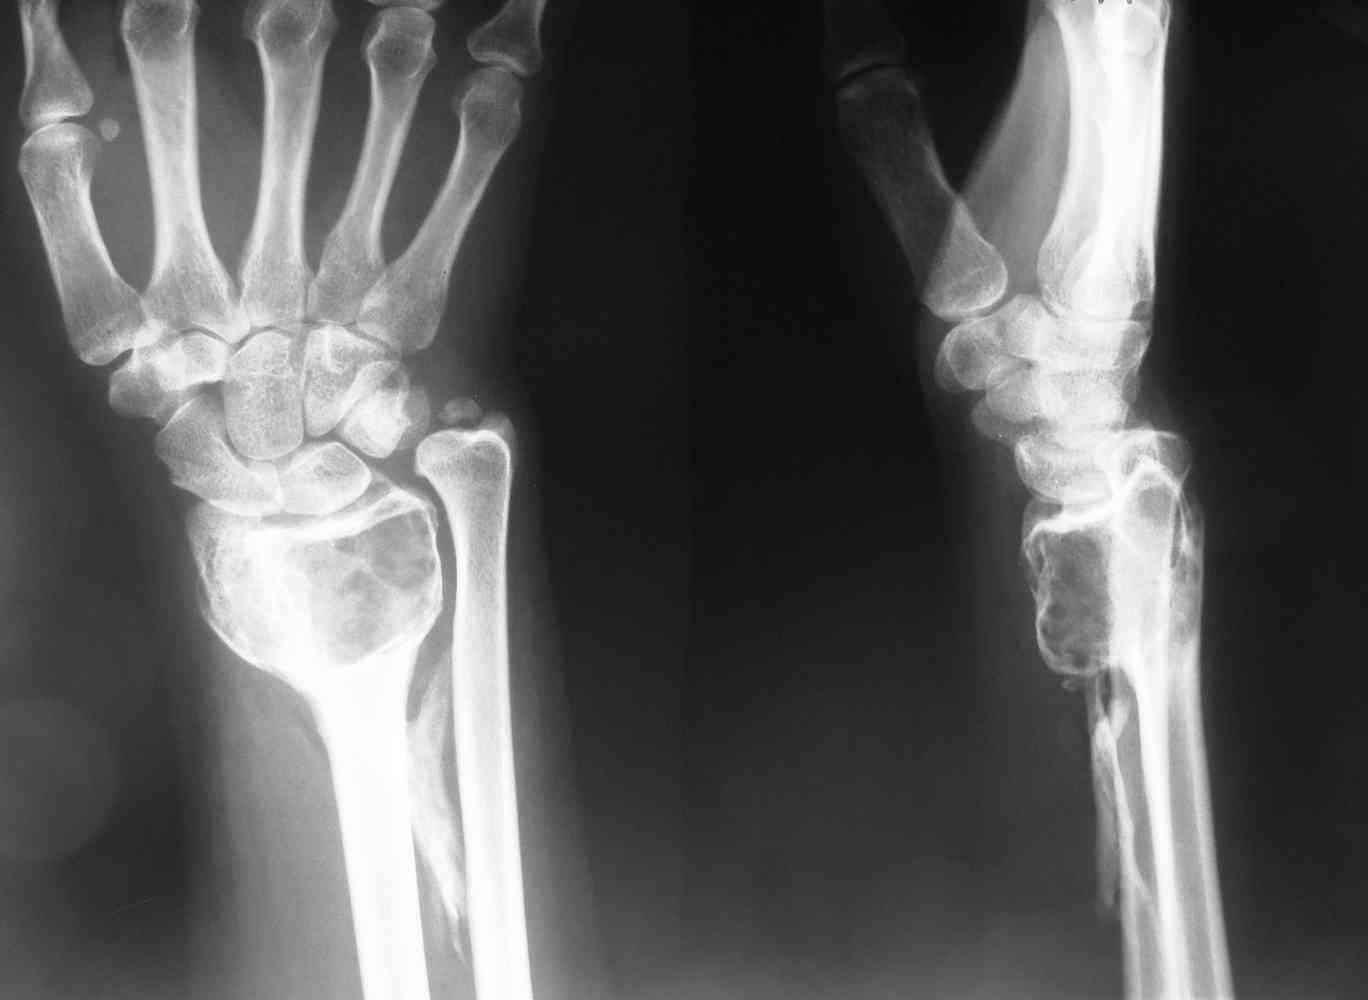

ОБК дистального эпифиза левой лучевой кости

Здравствуйте, уважаемые коллеги! На приём обратилась молодая женщина 28 лет с жалобами на наличие образования в области левого лучезапястного сустава.

Болевой синдром умеренный, "ночных" болей нет. Полтора года назад - патологический перелом дистального эпиметафмза левой лучевой кости. В Областном онкодиспансере выполнена открытая биопсия патологического очага.

Морфологическое заключение: остеобластокластома без признаков малигнизации.